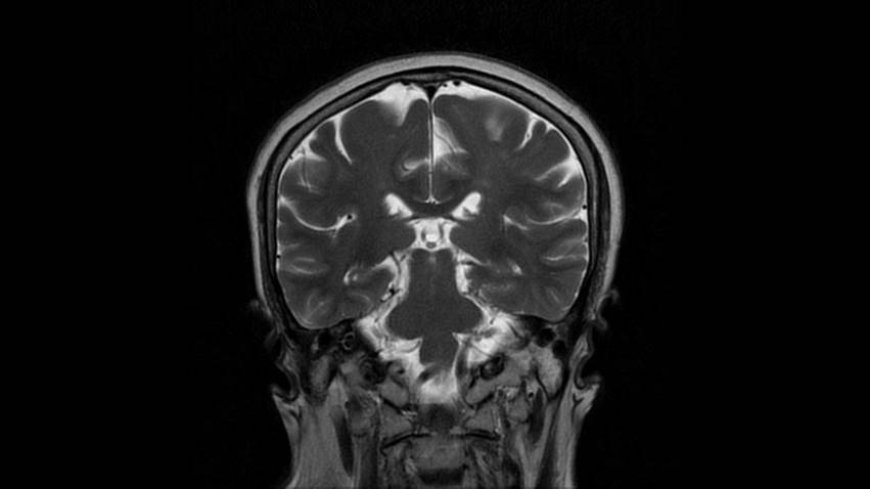

MRI of Brain

Coronal T2